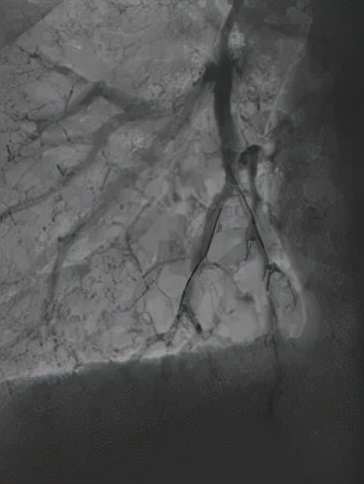

△球囊扩张狭窄血管

△球囊扩张后复查,血管血流明显改善